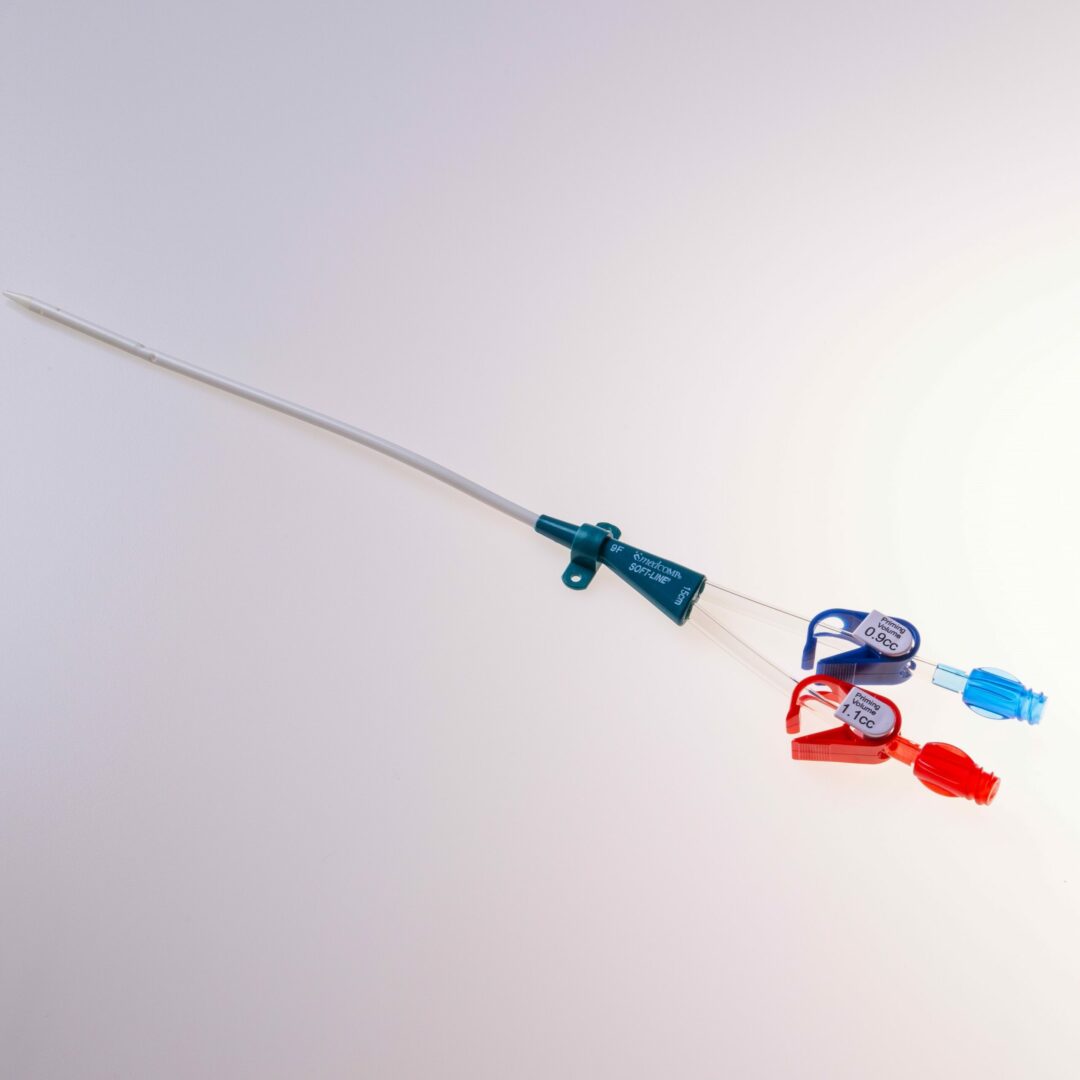

Tip Design

Der Softline® verfügt über ein konisches Spitzendesign und weist einen Lumendurchmesser von 7 French oder 9 French auf.

Produktbeschreibung

Der Softline® erfüllt eine wichtige Überbrückungsfunktion, indem er als temporäre Lösung dient, bis ein möglicher permanenter Zugang etabliert und einsatzbereit ist oder bis zur erfolgten Nierentransplantation. Dieser Katheter ist speziell entwickelt, um den Anforderungen pädiatrischer Patienten gerecht zu werden und ihnen eine optimale Behandlung zu ermöglichen.

Die Einführung in das Gefäß erfolgt über den Führungsdraht.